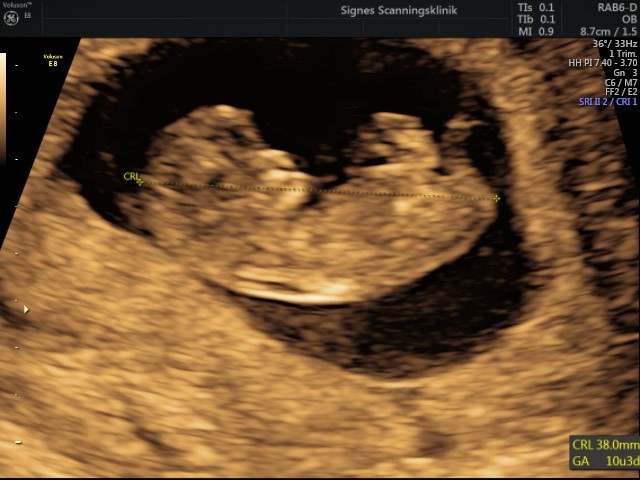

Alt så fint ud og den lille baby hyggede sig rigtig meget derinde. Blev sat til at være en dag længere henne, igen så den vokser godt!

Vedhæftede fotos (klik for at se i fuld størrelse)